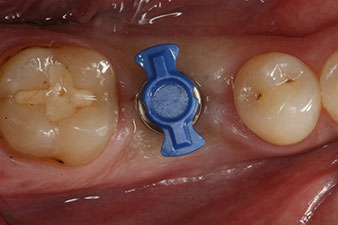

After healing of the soft tissue, the implant stability was measured again before delivery of the prosthetic restoration.

Both values were virtually unchanged and were between the medium and the high range – where the lower value is always used as the reference value that determines the treatment.

Therefore, successful osseointegration and adequate biological stability could be recorded, which enabled an impression to be taken in the same session.